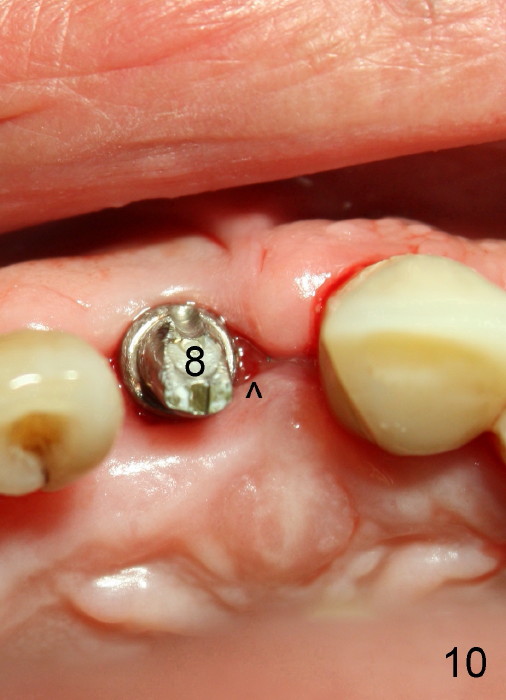

The insertion torque for the implants (4.5x20 mm and 4x20 mm) are 40 and 60 Ncm for #8 and 9, respectively (Fig.7). The stability is probably due to the fact that these two implants are engaged into the two cortical plates of the sockets (arrowheads). Allograft is placed in the mesiodens sockets. Immediate provisionals are fabricated. Fig.8,9 show the provisionals 18 days postop. One of the provisionals (#8) is dislodged 5 weeks postop. Before recementation of the provisional (Fig.10), healthy granulation tissue is found next to the implant (^).